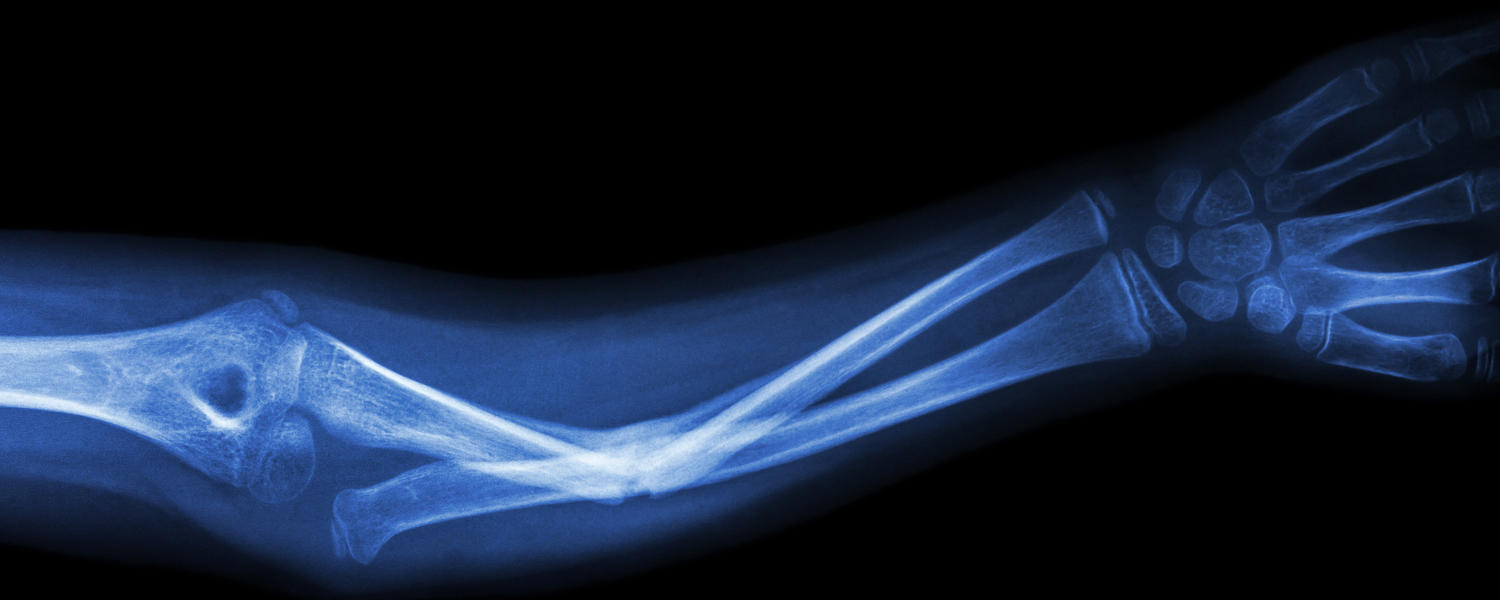

Numerous faculty members have achieved national and international funding support and award recognition for diverse clinical, health services, translational, and basic science research. Research programs include clinical and advanced imaging research following trauma and soft tissue injury, osteoarthritis clinical and basic science research, translational musculoskeletal oncology and spine research, and many others.